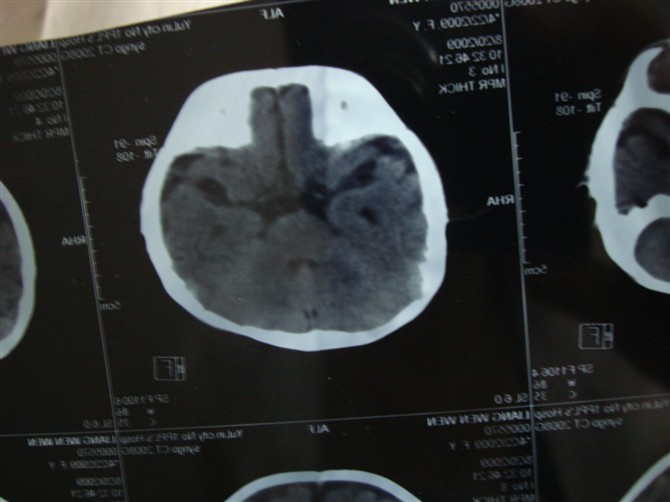

朋友的女儿,被玉林市第一人民医院医院诊断脑积水,各位老师帮忙看下!

顺产,无缺氧史,经常哭闹,无其它不适!

相机照的不太清楚,但还是请各位老师帮忙看下,谢谢!

考虑外部性脑积水。

胼胝体发育不良,外部性脑积水。脑白质密度减低,hie后遗症?

图像不连续,外部性脑积水诊断问题不大,另外,三脑室上抬,侧脑室间距增宽,支持考虑胼胝体发育不良。